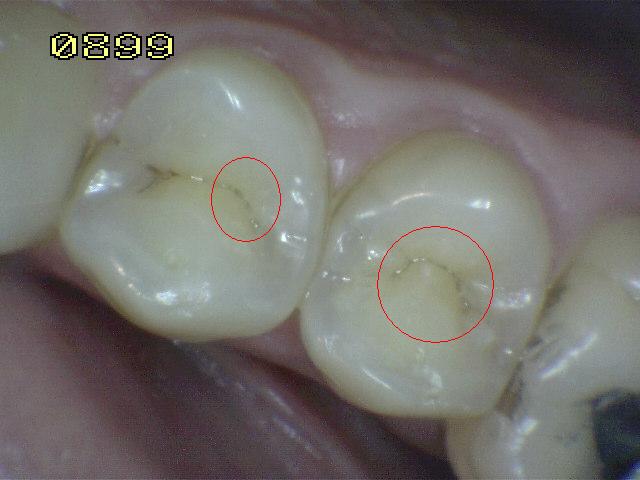

Código 5:

Cavidad detectable con dentina visible hasta la

mitad de la superficie

- Hay una cavidad en el esmalte opaco

o decolorado, dejando al descubierto la dentina. El diente

visto en estado húmedo puede haber oscurecimiento de la

dentina visible a través del esmalte. Una vez seco, hay

evidencia visual de la pérdida de la estructura del diente a la

entrada o dentro de la fosa o fisura, cavitación franca

> 0,5 mm hasta la mitad de la superficie dental. Hay evidencia visual de

desmineralización ( blanco opaco, de color marrón o paredes negras

ó de color marrón) en la entrada o dentro de la fosa o fisura. A juicio

del examinador se observa dentina expuesta en el piso y paredes de la

cavidad.

- La sonda de la OMS / IPC / PSR

se puede utilizar suavemente para confirmar la presencia de una

cavidad, al parecer en la dentina. Esto se consigue deslizando el extremo de la bola a lo

largo de la fosa o fisura sospechoso y una cavidad de la dentina se

detecta si el balón entra en la abertura de la cavidad y en la opinión

del examinador en la base de la cavidad se encuentra la dentina.